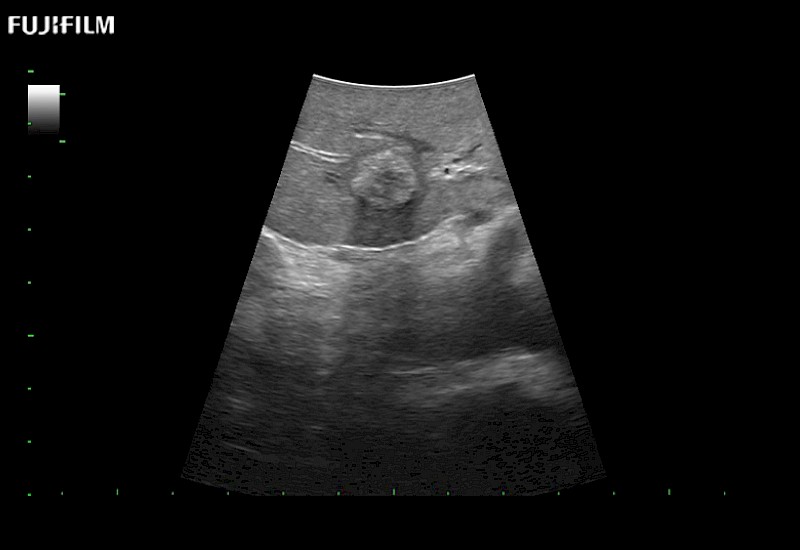

Exclusive linear array 4-way laparoscopic transducer for better visualization of targeted lesions.